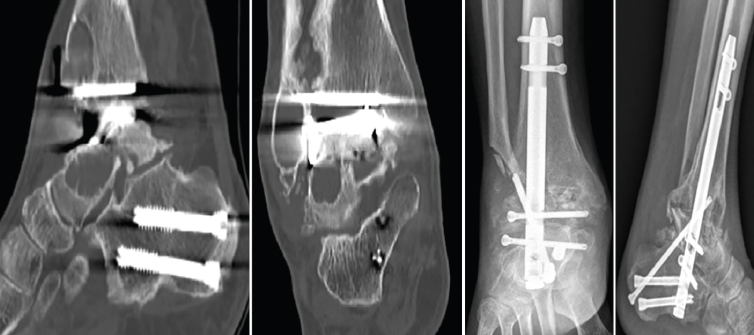

La paciente presentó un postoperatorio dentro de la normalidad pero, a los 2 años de evolución, empezó a presentar molestias en el tobillo. Se realizaron Rx y TAC donde se objetivó consolidación de la articulación subtalar pero pseudoartrosis a nivel tibiotalar, con rotura incompleta del clavo y del cerrojo del calcáneo colocado en sentido posteroanterior.

En este caso, la extracción fue sencilla: una vez retirados los tornillos de bloqueo, se realizó, con el sistema extractor del clavo, la extracción del mismo sin dificultad, ya que se trataba de una rotura incompleta. Realizamos un nuevo legrado de las superficies óseas, perforación de las mismas, nuevo aporte de injerto de cresta ilíaca y fijación con placa de artrodesis tibiotalar (Palex Medical), ya que la articulación subtalar estaba consolidada (Figura 6).

Figura 4. Imágenes de tomografía computarizada con lisis alrededor de la prótesis con deformidad en varo. Se aprecia la osteosíntesis para la osteotomía del calcáneo realizada previamente. Imágenes radiográficas tras la artrodesis tibiotalocalcánea con clavo retrogrado con tornillo tibiotalocalcáneo del calcáneo a la tibia oblicuo.